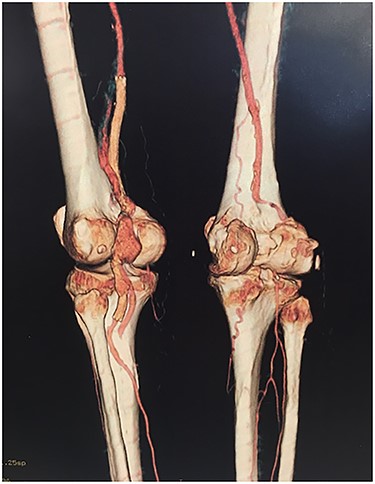

Based on the characteristics of the pseudoaneurysm, we decided on a minimally invasive interventional approach. This was in agreement with other vascular surgeons and the family. Under local anesthesia, the left common femoral artery was punctured in antegrade fashion, and an 8-F sheath was deployed. An X-ray of the popliteal region highlighted the stent fracture, and digital arteriography showed the large pseudoaneurysm. After administration of 5000 IU of heparin, a 0.035 guidewire was passed across the fractured stent and was placed distally in the posterior tibial artery. At the end of the procedure, a 7.0 × 150-mm self-expandable Viabahn endoprosthesis (W. L. Gore & Associates, Flagstaff, AZ, USA) was delivered into the stent, and adjuvant balloon inflation was performed with a 6.0 × 80-mm balloon leading to a complete exclusion of the pseudoaneurysm (Fig. 4). The final angiogram showed no residual stenosis, complete exclusion of the pseudoaneurysm, and no compromise of distal runoff. There were no complications associated with the procedure.

Viabahn endoprosthesis delivered after percutaneous intervention and immediately intraoperative angiogram.